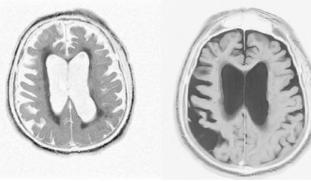

Alzheimer’s disease (AD) is associated with prion-like aggregation of the β-amyloid and Tau proteins, that form neurotoxic aggregates in the brain. Studies have pointed out the association between brain-localized bacteria and AD; however. Recently, we identified that bacterial DNA can aggregate Tau protein (Tetz et a, 2020). We will explore whether DNA from brain-localized bacteria triggers β-amyloid misfolding; thus, being, a previously overlooked cause of AD.